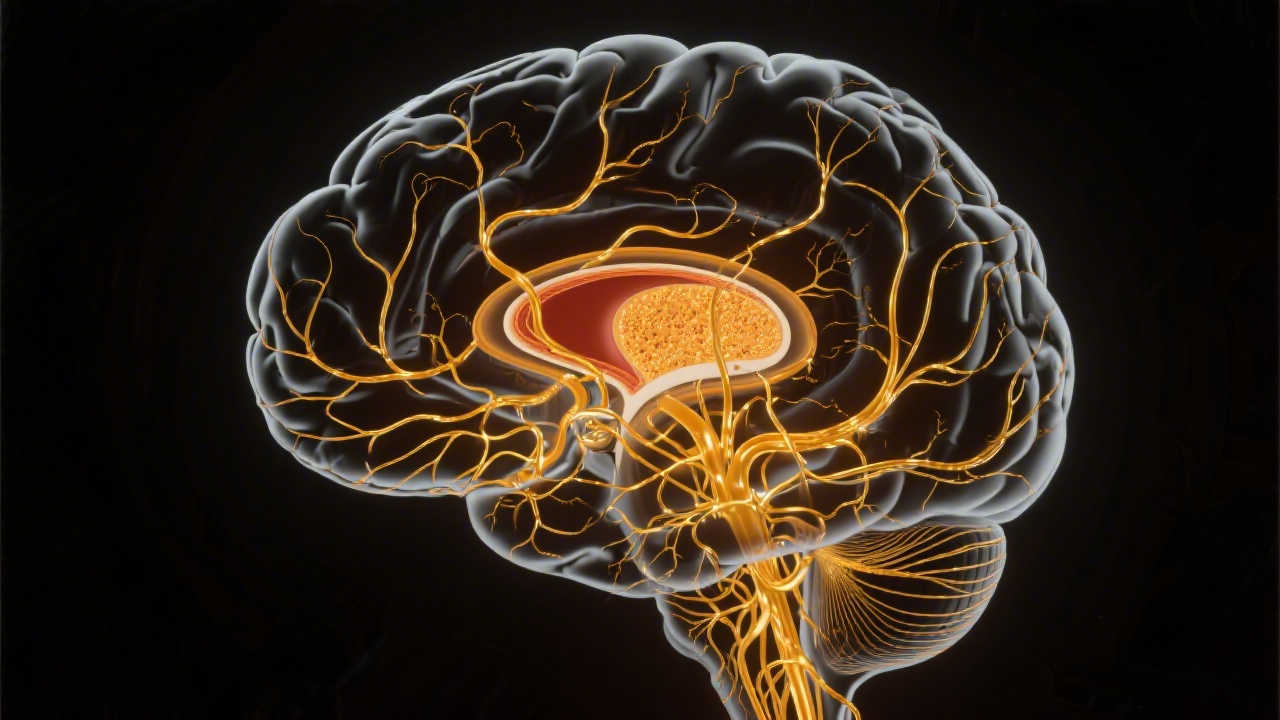

The Basal Ganglia: Movement Selection and Reward

The basal ganglia is a collection of subcortical nuclei - including the striatum (caudate + putamen), globus pallidus, subthalamic nucleus, and substantia nigra - that form a critical loop with the cortex and thalamus. Primarily understood as a movement selection system, the basal ganglia also plays important roles in reward processing, habit formation, and procedural memory.

Its relevance to sleep emerges through several channels: basal ganglia dysfunction directly causes some of the most prevalent sleep disorders; the dopaminergic reward system (heavily involving the basal ganglia) affects sleep timing and quality; and procedural memory consolidation during sleep involves basal ganglia-dependent circuits.